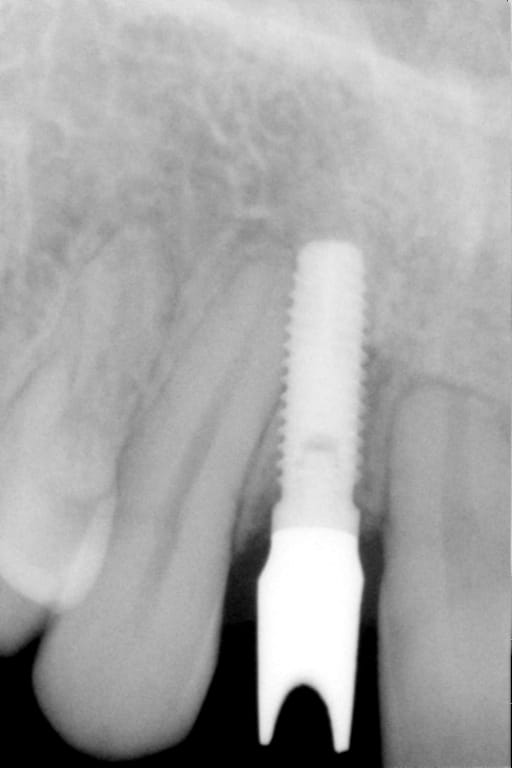

On m'a dit que Pluton était incollable sur les implants.

Alors, j'aimerais demander à Pluton s'il sait ce que c'est...

dis m'en un peu plus sur ce cas car c'est un implant avec un hexagone externe et j'ai beaucoup de correspondances....

cela dit, hex externe en général c'est une plateforme standard et quasi toutes les marques sont compatibles

donc çà limite un peu les recherches sur les marques disponibles en france à cette époque et la marque d'implant qui match le plus avec les caractéristiques que tu m'as montré (hex externe, apex plat, spires en V, col large, vis de cicat avec hexagone....) c'est un implant Biomet 3i osseotite parallel walled